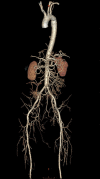

A 67-year-old man with diabetes and hypertension presented with complaints of abdominal pain and lower back ache for 7 months, with intermittent episodes of fever. On examination, there was an expansile mass in the upper abdomen with bruit on auscultation. He also had tenderness in the L1-L2 vertebral space with paraspinal fullness, causing painful restriction of lower limb motor functions but without affecting sensation. On evaluation, he was found to have an abdominal aortic aneurysm with infective lumbar spondylodiscitis. The aspirate from the paravertebral infected tissue and cultures from blood grew Pseudomonas aeruginosa, a rare causative agent of mycotic aortic aneurysm. Whether the infective spondylitis spread to the abdominal aorta causing the mycotic aneurysm or vice versa is a dilemma in such a case. However, the mainstay of treatment remains adequate source control and repair of the aneurysm with appropriate antibiotic therapy. Our patient received intravenous antibiotics for P . aeruginosa based on sensitivity, following which he underwent debridement of the infective spondylodiscitis with aneurysmorrhaphy. He had an uneventful recovery and was well at 3-month follow-up.